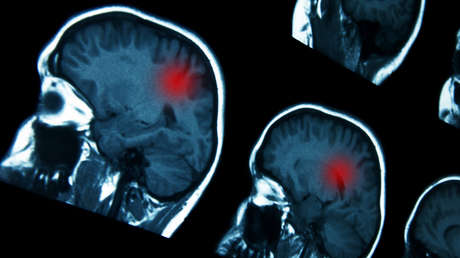

El uso prolongado de ciertos progestágenos, fármacos hormonales que se usan para tratar trastornos ginecológicos, se asocia a un mayor riesgo de desarrollar un tipo de tumor cerebral conocido como meningioma intracraneal, según un estudio publicado este miércoles en la revista médica The BMJ.

Así, se concluyó que el uso prolongado (un año o más) de medrogestona se asoció a un riesgo 4,1 veces mayor de padecer meningioma intracraneal que requiriera cirugía, mientras que el uso prolongado de acetato de medroxiprogesterona inyectable se asoció a un riesgo 5,6 veces más alto, y el uso prolongado de promegestona se relacionó con un riesgo 2,7 veces mayor. Sin embargo, no parece existir tal amenaza si estos progestágenos se utilizan por menos de un año.